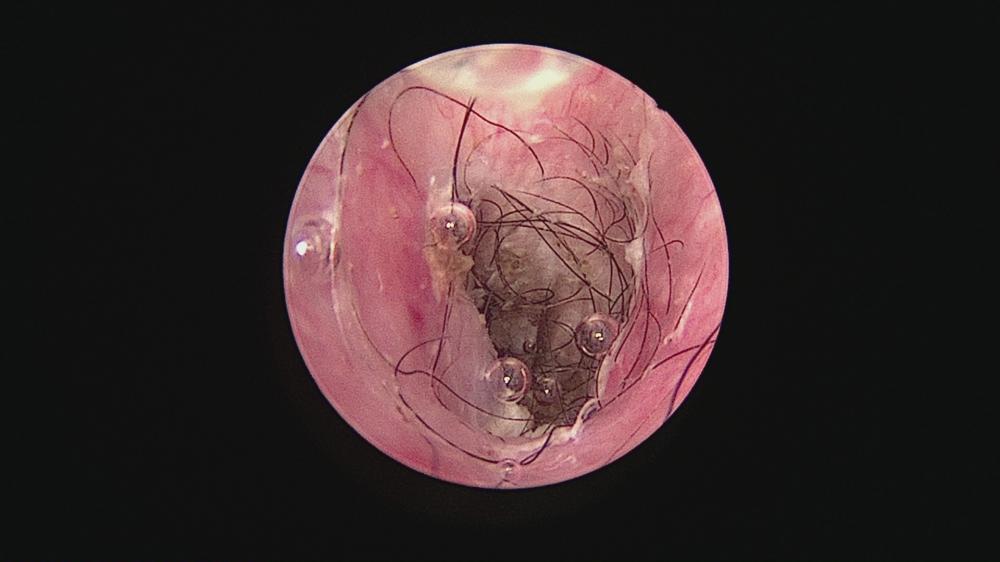

・耳垢や毛、ポリープや異物などを除去することで本来の環境に近づける